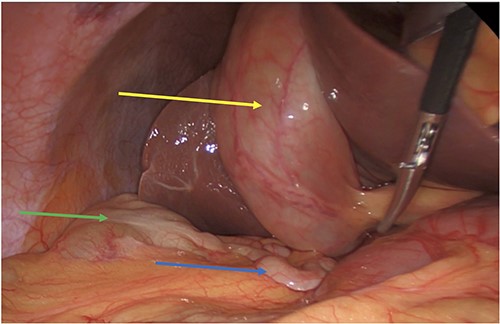

Intraoperatively she had severe inflammation at the Calot’s triangle, and we performed a retrograde, fundus down and cholecystectomy. She was noted to have a subhepatic appendix along with a high riding cecum (Figs 1 and 2). The appendix was not involved in the gallbladder inflammation (Fig. 4).

Post cholecystectomy with the subhepatic appendix overlying the left lobe of the liver (yellow arrow) and the cecum (blue arrow) next to the hepatic flexure (green arrow).